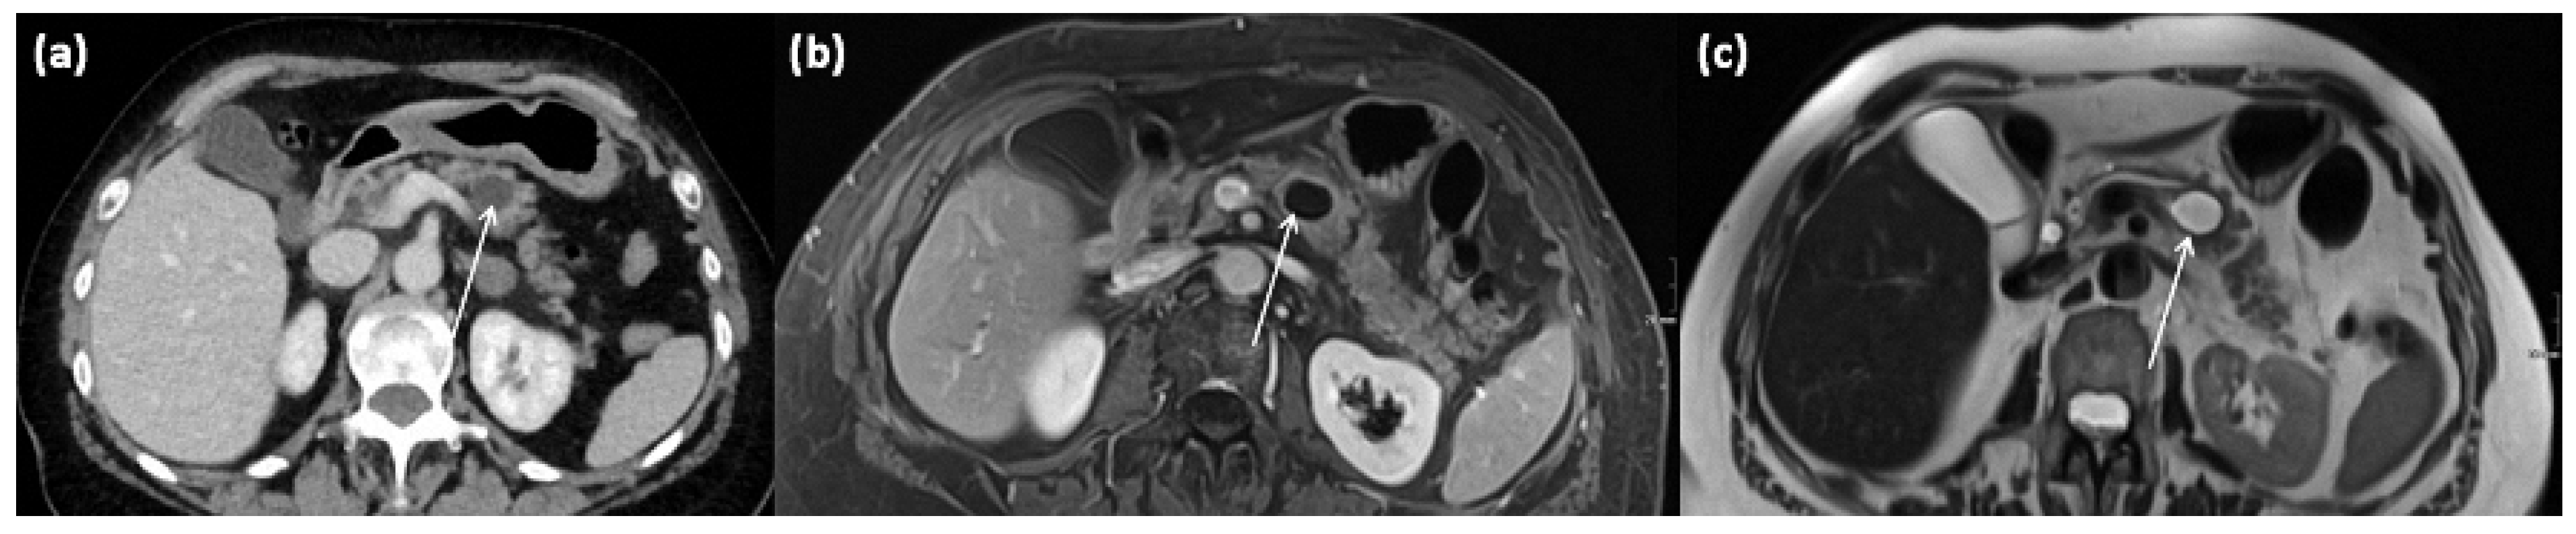

Figure 11.

Axial CT in portal venous phase (a) and axial MRI with T1w after gadolinium-based contrast administration (b) as well as T2w native (c) in a 64-year-old female patient. In the pancreatic body, a sharply demarcated, roundly configured, cystic lesion is present, fit to a branch duct IPMN (arrows). There are no main duct dilatation, solid parts, or vegetations. T2w shows a homogenous hyperintense signal.